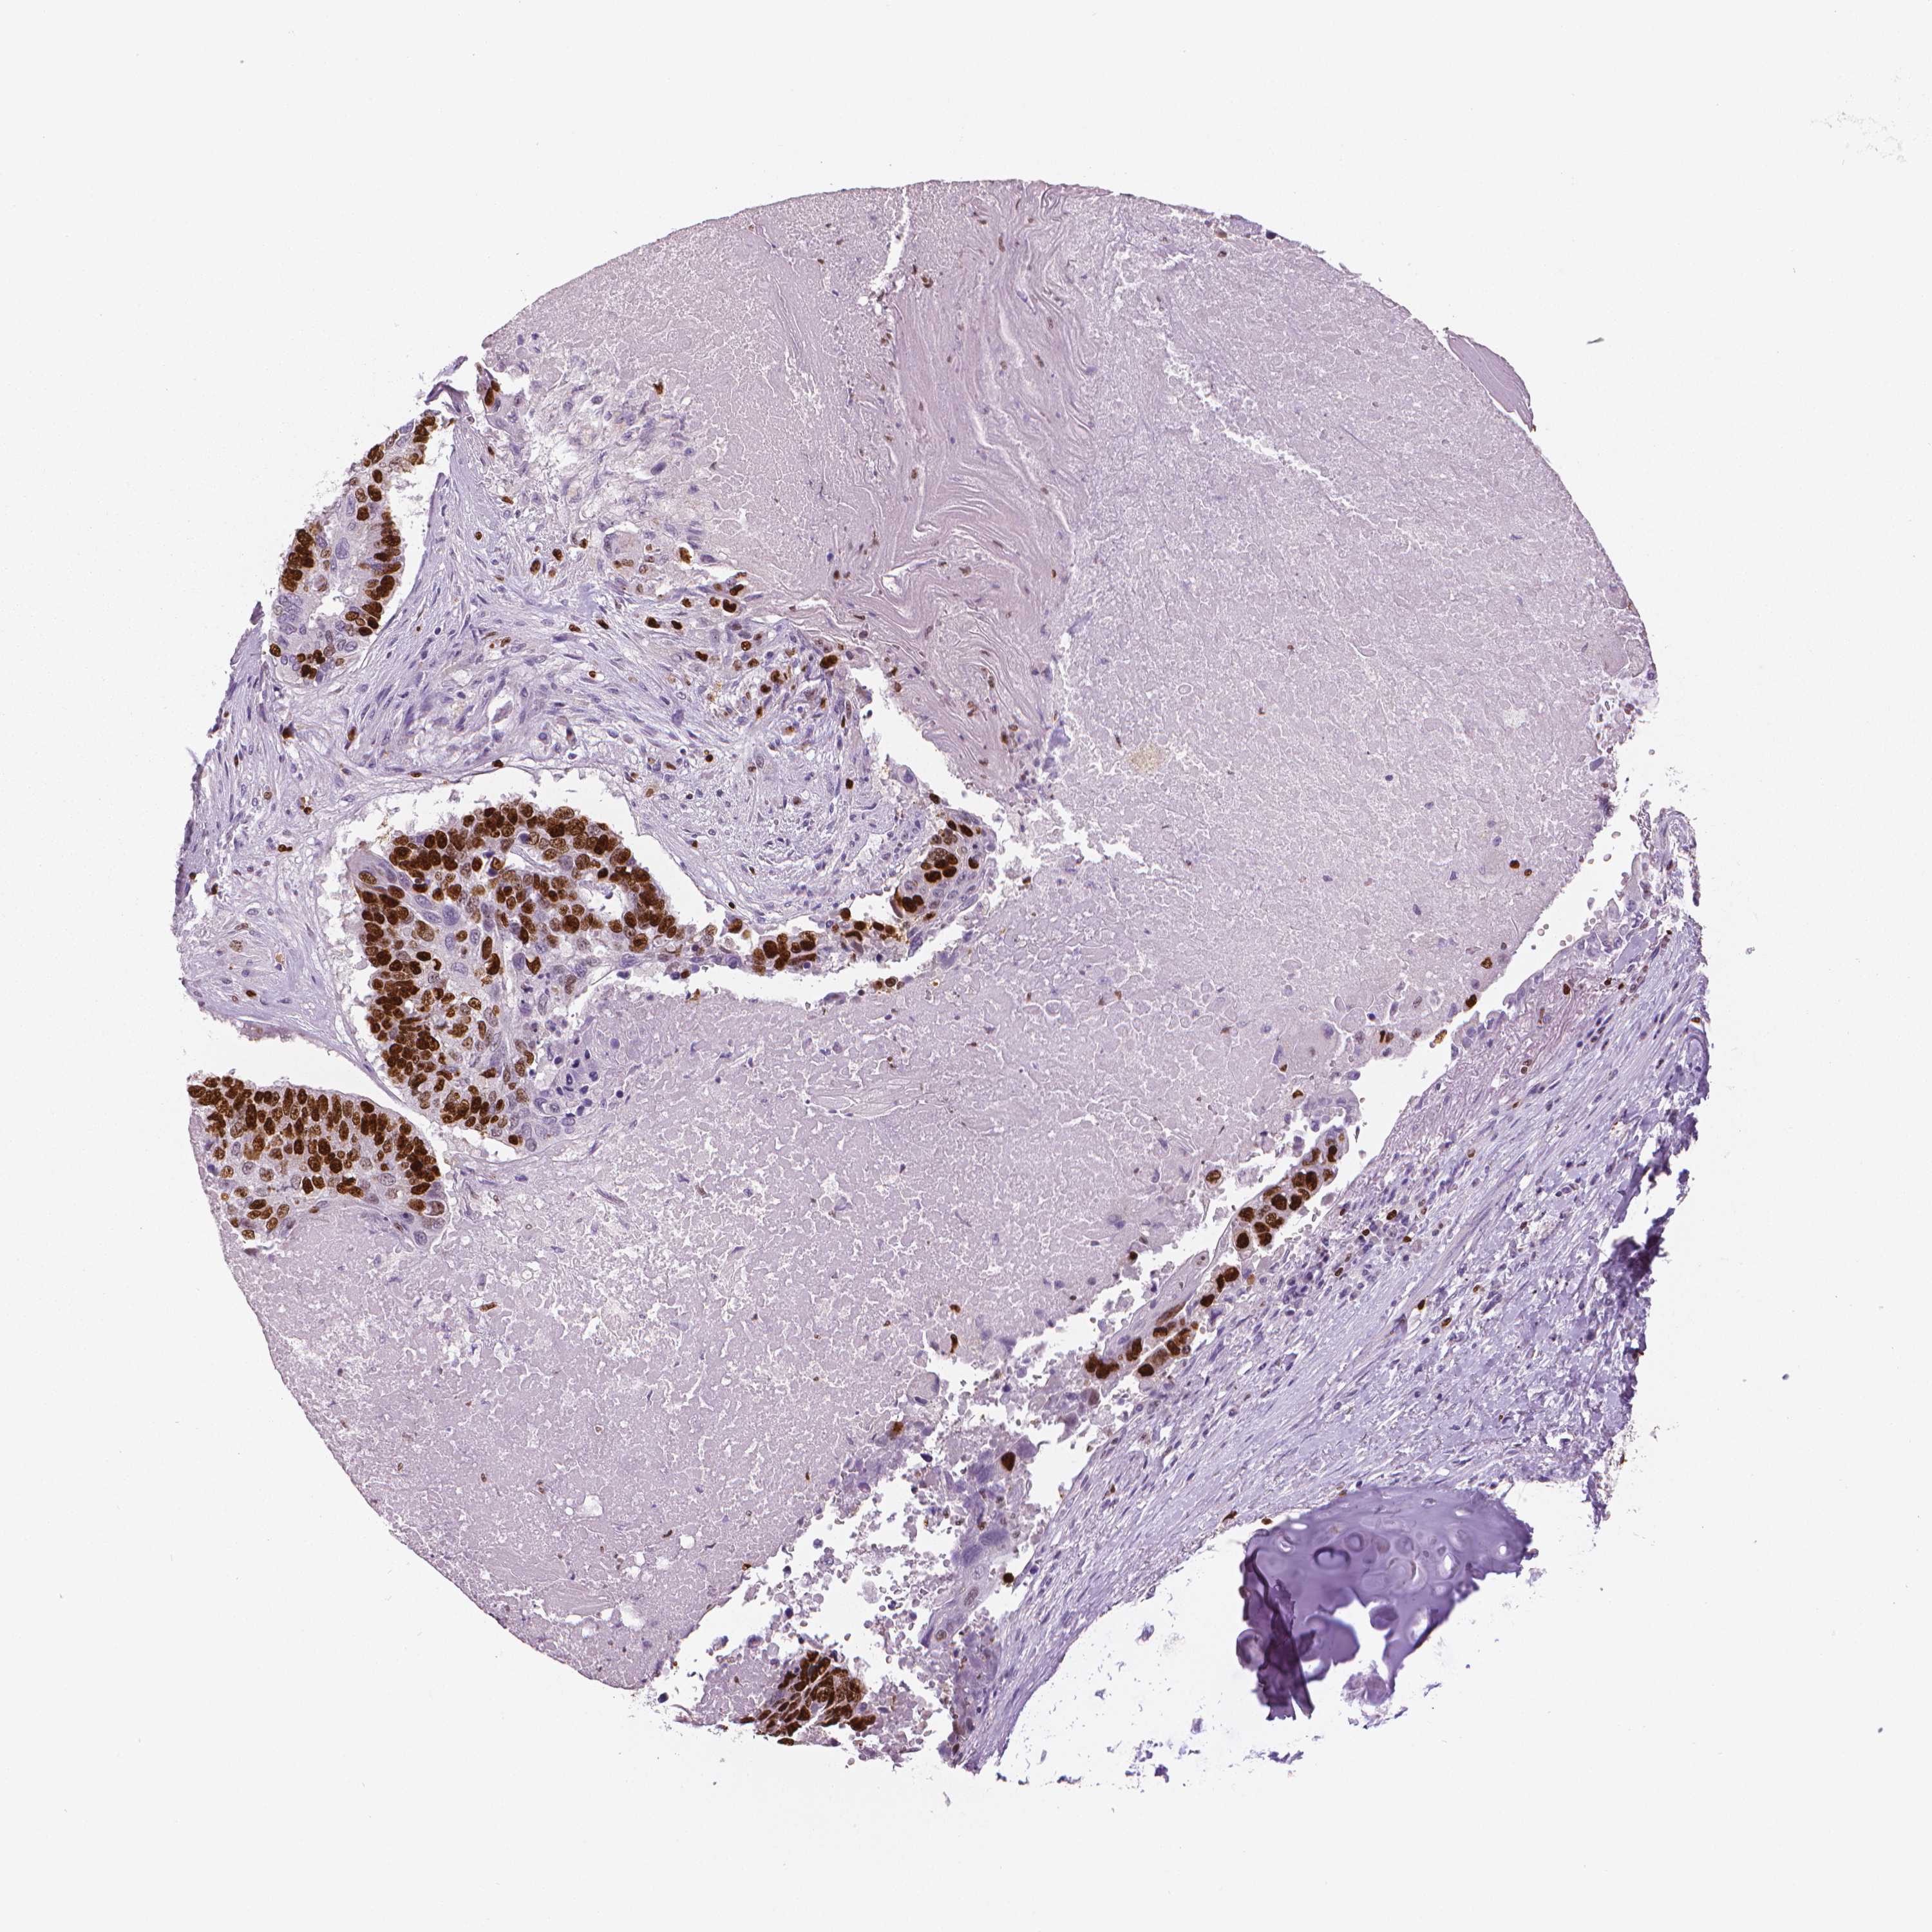

CANCER LUNG CANCER Show tissue menu

LUAD TCGA LUAD VALIDATION LUSC TCGA LUSC VALIDATION PROTEIN LUAD CPTAC PROTEIN LUSC CPTAC PROTEIN EXPRESSION

ANTIBODIES

AND

VALIDATION